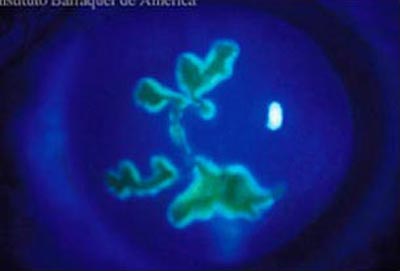

La forma más frecuente de la queratitis herpética es la ulcera dendrítica, que es una lesión lineal ramificada con bulbos terminales y bordes inflamados que contienen virus vivos. Se tiñe positivamente con fluoresceina lo que facilita su diagnóstico; compromete el epitelio pudiendo alcanzar la membrana basal en la etapa inicial. Produce sensación de cuerpo extraño, lagrimeo y visión borrosa.

Cuando la úlcera pierde su caracter lineal, se la conoce como “ ulcera geográfica” que representa a una lesión dendrítica extendida y se asocian a una mayor duración de los síntomas y con frecuencia al uso previo de corticoides.

Herpes Simple

Herpes Simple